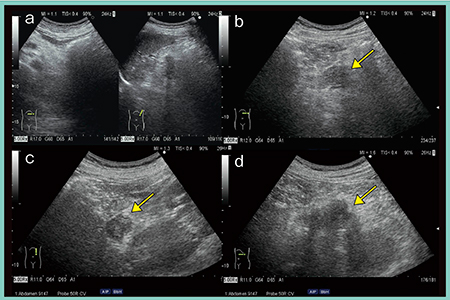

まず,膵臓全体の長軸像と,上腸間膜動脈が見えてくる部分から膵体部までの2カットを1枚目とする(図1 a)。次に,プローブを縦にして走査し,膵頭部と,膵体部から膵尾部の脾臓に至る部分までの2カットを2枚目とする(図1 b)。膵癌は約7割が膵頭部に発生するため,非常に多くの情報を含む膵頭部の縦の走査による画像は,スクリーニングに必須である。最後に,左の季肋部から左の側腹部に向けた横走査を行うことで,脾静脈の上に膵臓が描出される(図1 c)。この走査は一般的にあまり行われていないが,必ず追加すべき1枚である。通常行っている左肋間走査では膵臓は不明瞭なことがあるが,それは膵臓への脂肪浸潤のため脂肪肝と同様に超音波が減衰することも原因である。そのため,直角に超音波ビームが当たるこの横走査は非常に重要であり,膵管が直交して描出されるメリットもあり必要なカットである。

図1 膵臓のスクリーニングに必要な超音波画像

膵頭部は主膵管と総胆管の合流部で,ここに発生する癌は膵内胆管や主膵管の閉塞を伴い,十二指腸や上腸間膜動脈(SMA),上腸間膜静脈(SMV)に浸潤する。尾側の膵管が数珠状に拡張している様子が典型像として得られる(図2 a)。

膵頸部は膵頭部と膵体部の移行部で,門脈からSMVの腹側に位置しており,ここに発生する癌は膵外進展,腹腔動脈や総肝動脈への浸潤,主膵管への浸潤がある(図2 b)。胃の前庭部に浸潤しやすく,プローブを上に振り上げて観察することで,見逃し防止につながる。

膵鉤部はSMVの背側,SMVより左側に位置する。ここに発生する癌は膵外進展が強く,十二指腸水平脚やSMA,SMVに浸潤するほか,神経周囲浸潤も多い。また,後腹膜の深部に進展していくため,膵臓の腫瘍に気づきづらい。そのため,必ず十二指腸が見えなくなるところまでしっかりと観察することが重要である(図2 c)。

グルーブ領域は,十二指腸下行脚と膵頭部,総胆管に囲まれた溝(groove)を指し,ここに発生する癌は十二指腸や膵内胆管に浸潤する(図2 d)。グルーブ膵炎との鑑別診断も困難であり,十分注意して観察する必要がある。

このほか,膵体部に発生する癌(図2 e)は脾動脈,脾静脈に浸潤し,膵尾部に発生する癌(図2 f)は脾臓や脾門部に存在する消化管に浸潤するという特徴がある。